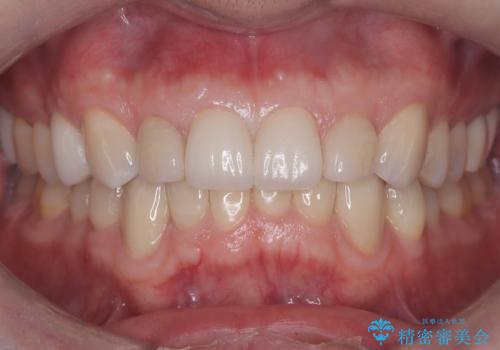

保険診療の黄ばんできた前歯をオールセラミッククラウンで自然な歯に